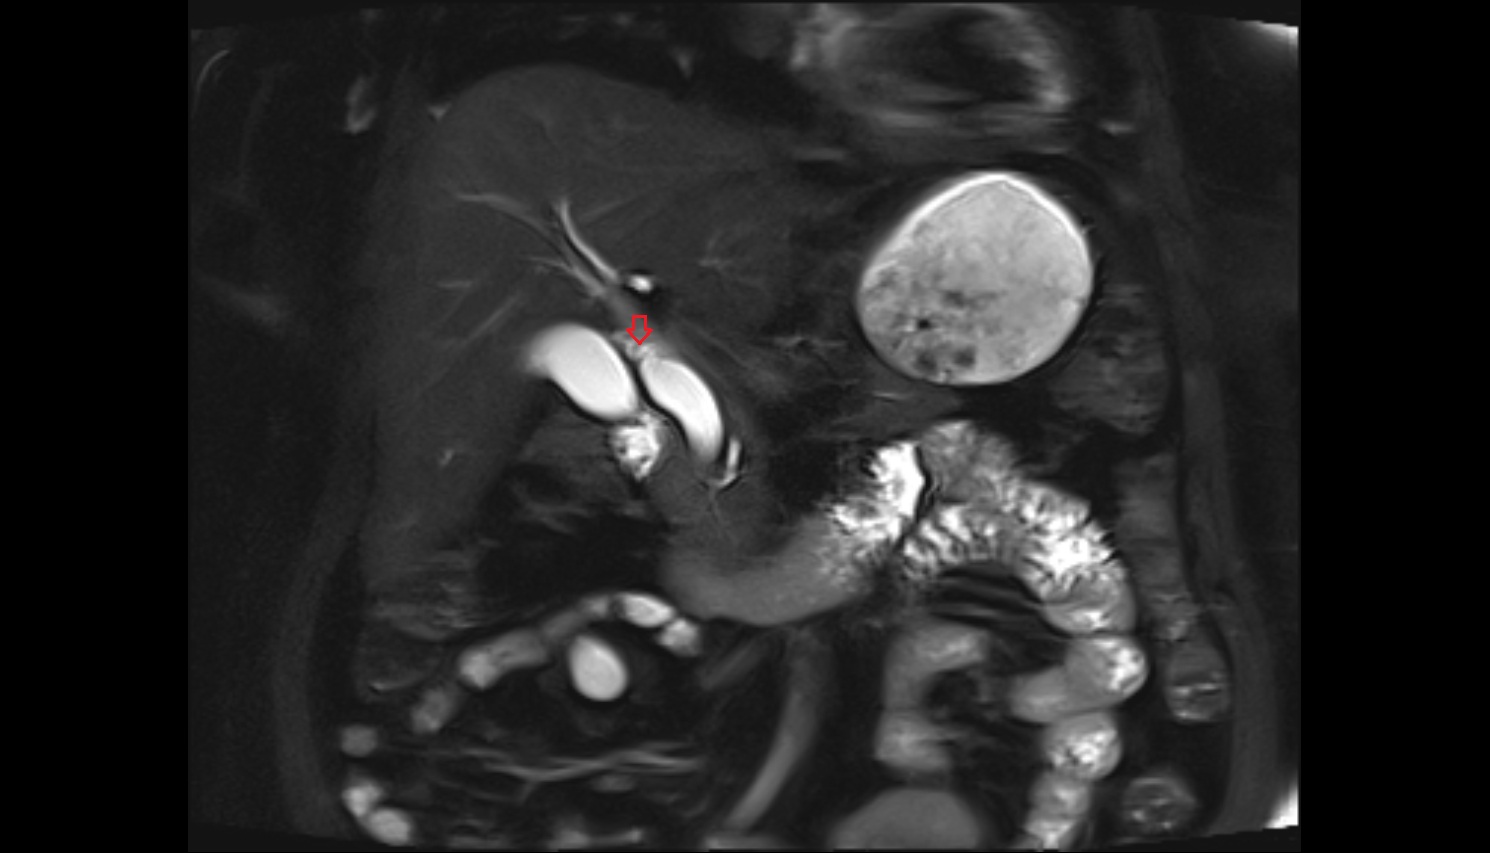

- Common bile duct

- Pancreatic duct